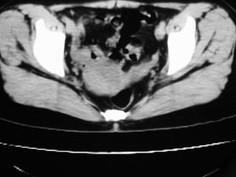

女42岁肛门下坠感4月余.

子宫轻度右倾,体后方见小似新月形低密度区,边界清楚。余所见无明显异常。

考虑:子宫直肠窝少量积液(盆腔炎所致)。

子宫轻度右倾,体后方见小似新月形低密度区,道格拉斯窝周围间隙欠清晰,有索条模糊影阴,多考虑:肛周脓肿可能性大。

子宫轻度右倾,体后方见小似新月形低密度区,道格拉斯窝周围间隙欠清晰,有索条模糊影阴,多考虑:肛周慢性感染可能。